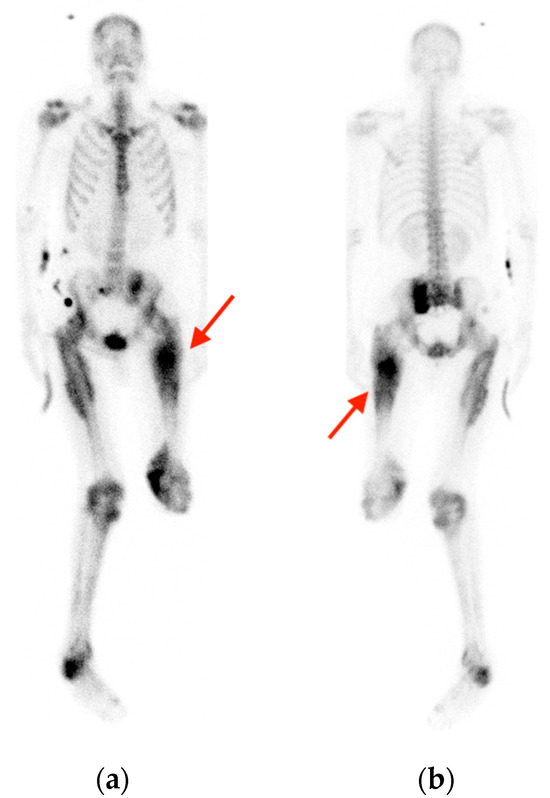

2.1. Fracture